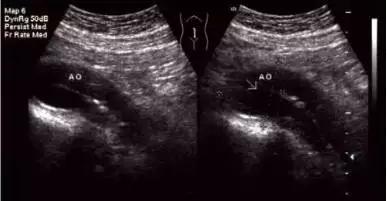

2.患者禁食12h空腹状态下进行经腹部超声检查。将探头置于腹部,可显示腹主动脉病变。

1.二维超声检查,主要观察主动脉有无增宽,其内有无异常回声。

①主动脉瘤表现为主动脉局限性增宽,增宽的动脉腔内有时可见附壁血栓形成。

②主动脉夹层在二维超声上表现为病变部位主动脉增宽,其内可见丝裂的内膜反射,该内膜将增宽的主动脉分为真假两腔。

③有时可显示真假两腔相交通之处,表现为撕裂的内膜上有回声中断。假腔中常可显示云雾状回声反射和附壁血栓